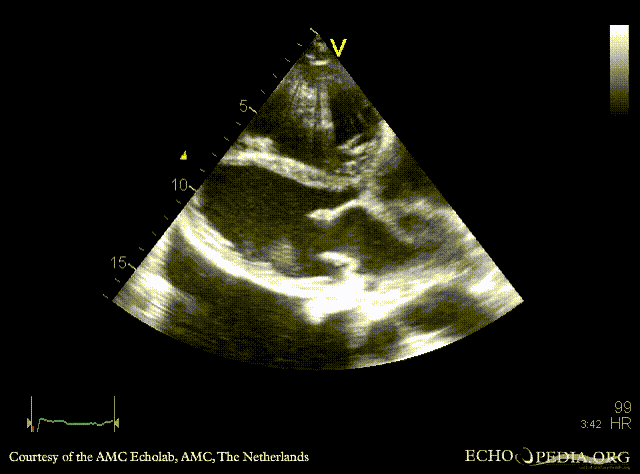

E00452.gif E00453.gif

PSAX: flattening of IAS, enlarged right ventricle PSAX: prolaps of PMVL